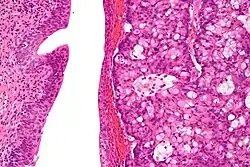

The urachus is also subject to neoplasia. Urachal adenocarcinoma is histologically similar to adenocarcinoma of the bowel. Rarely, urachus carcinomas can metastasise to other regions of the body, including pelvic bones and the lung.[7]

High magnification micrograph of a urachal carcinoma. H&E stain

High magnification micrograph of a urachal carcinoma. H&E stain